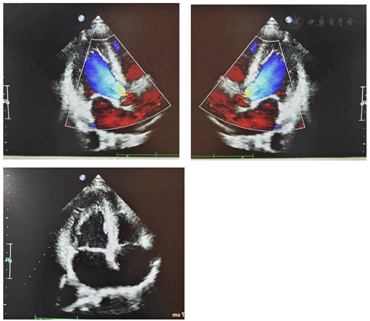

相关检查:血常规、肝肾功、血脂、血糖、尿蛋白及微量白蛋白、胸片、皮质醇节律、血浆甲氧基肾上腺素类物质未见异常。电解质:K 2.03mmol/L。心电图:窦性心律;ST-T改变(图1)。心脏彩超:左房稍增大(前后径35 mm)(图2)。动态血压监测:白天平均血压134/88 mmHg,夜间平均血压134/83 mmHg,全天平均血压134/86 mmHg。高血压五项(立位):血管紧张素活性1.99 uIU/ml/h,醛固酮539.00 pg/ml,血管紧张素Ⅱ 11.40 pg/ml,皮质醇326.00ng/ml,促肾上腺皮质激素36.30 pg/ml。高血压五项(卧位):血管紧张素活性<0.5 uIU/ml/h,醛固酮634.00 pg/ml,血管紧张素Ⅱ<5 pg/ml,皮质醇233.00 ng/ml,促肾上腺皮质激素37.10 pg/ml。肾上腺CT(增强):左侧肾上腺体部小结节,考虑小腺瘤,请结合临床及其他检查(图3)。双侧肾上腺静脉采血:左侧肾上腺静脉两次采血结果分别为:①醛固酮40 150 pg/ml,皮质醇3 750ng/ml,醛固酮/皮质醇10.7;②醛固酮14 950 pg/ml,皮质醇2 010 ng/ml,醛固酮/皮质醇7.43;右侧肾上腺静脉两次采血结果分别为:①醛固酮676 pg/ml,皮质醇530 ng/ml,醛固酮/皮质醇1.27;②醛固酮629 pg/ml,皮质醇377 ng/ml,醛固酮/皮质醇1.66。下腔静脉采血:醛固酮1 265 pg/ml,皮质醇279 ng/ml。左侧肾上腺肿物活检:(左肾上腺肿瘤)肾上腺皮质腺瘤。免疫组化202102799-1:a-inhibin(+),Melan-A(+),CK(+),Syn(+),CEA(-),CgA(-),EMA(-),RCC(-),S-100(-),Ki-67(+)10%。